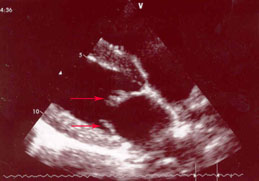

The picture below left is Chase's mitral valve from 2008, when he was three years old. You can see the red arrows that point to the leaflets that form the flap mentioned above. Compare that to the image on the right, which is Chase's uncle Indy, at 7 years old. The leaflet is very smooth and regular.

| Chase's Mitral Valve at 3 years |